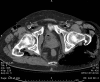

Fig. 2

Bubbles along the inferior limbs vessels